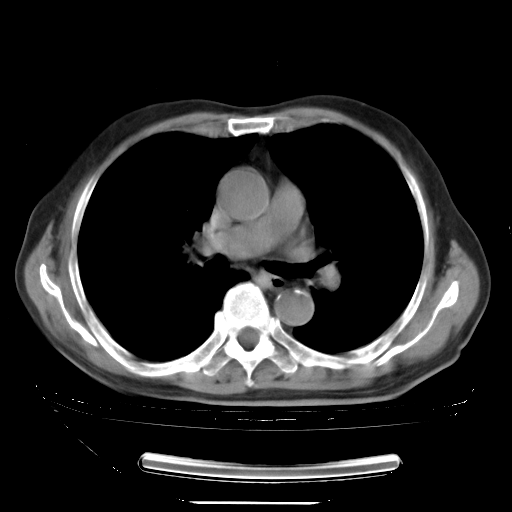

今天复查肺部CT,发现双肺广泛磨玻璃样改变。所以我把3月19日和5月9日相隔50天的肺部CT上传。请大家会诊。

2009年3月19日肺部CT片。

2009年3月19日肺部CT

5月9日肺部CT(在4月27日齐鲁医院肺部CT描述部分肺组织磨玻璃样改变,12天后肺组织广泛磨玻璃样改变)